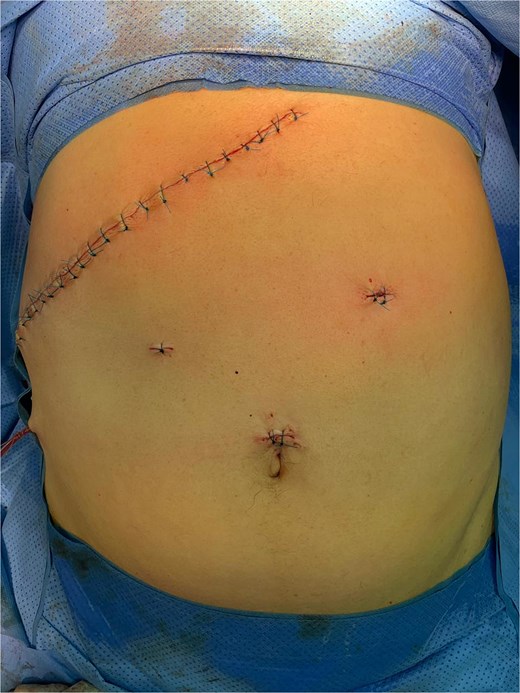

The initial laparoscopic approach was converted to right subcostal laparotomy (Fig. 2) due to unfavorable local conditions and severe inflammatory changes.

Surgical exploration revealed the true pathology: acute complicated cholecystitis with gallbladder fistulization to the subserosal gastric wall in the antro-pyloric region (Fig. 3), without mucosal involvement. The apparent ‘second gallbladder’ on imaging was actually a pseudocystic formation created by the fistulous communication and inflammatory process. The area was surrounded by significant inflammatory adhesions involving the omentum, creating a complex inflammatory mass.